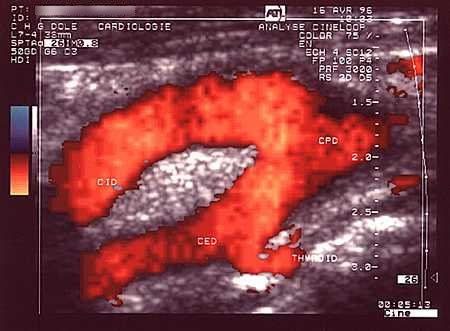

Doppler pulsatil, carotida comuna

Artera (in rosu) si vena (in albastru) vertebrala normale vizualizate in inter-transversara .

Doppler color.